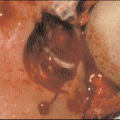

![]() 10.14 Severe ulceration in mixed vessel disease. This ulcer responded very well to larva therapy.